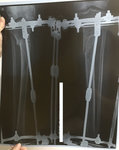

Рентген и ото ножек в 60 дней.

Срастаетесь, как молодые девчонки